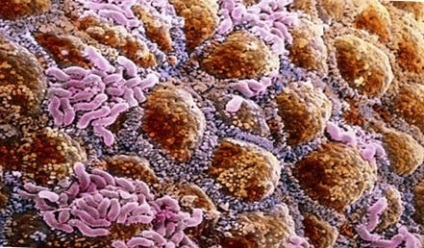

Fig. 4. Bacteriile care populează gura: mutanții Streptococcus (verde). Bakteroides gingivalis, cauzând periodontita (lila). Candida albicus (galben).

Fig. 5. Suprafața interioară a colonului. insulițe roz - grupuri de bacterii.